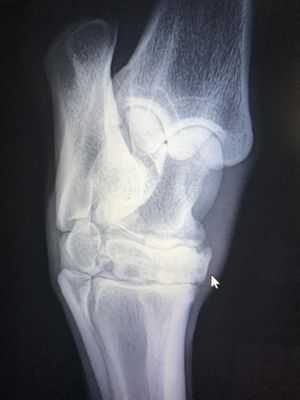

診断

●病歴

●臨床兆候

●身体診察

●臨床検査